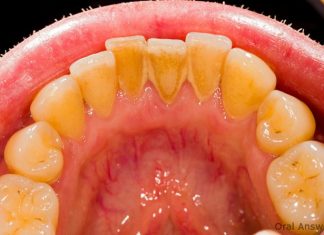

U današnjem članku vam pišemo na temu kako možete efikasno ukloniti zubni kamenac koristeći prirodne sastojke koje sigurno već imate kod kuće. Saznajte...

Problem kamenca...